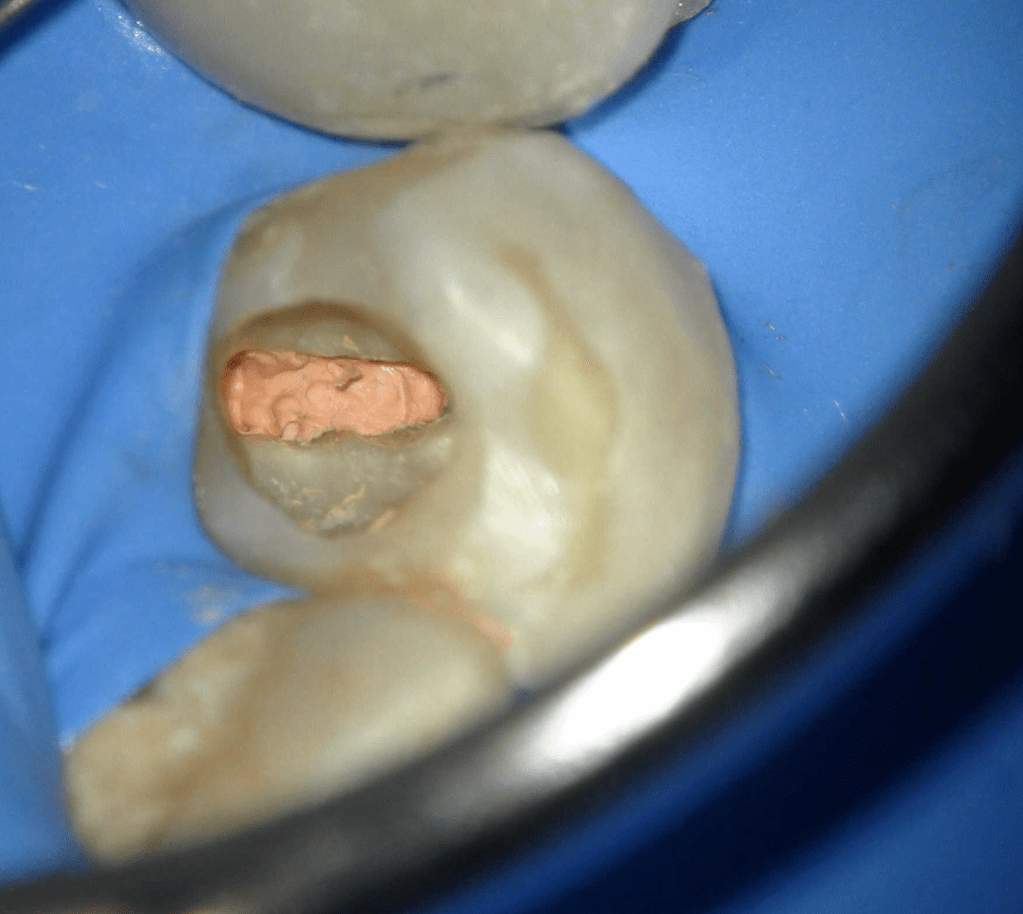

Fisura, remoción amalgama para explorar